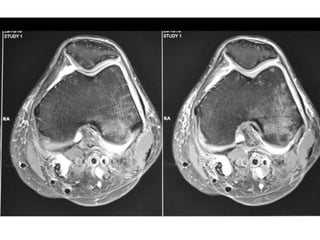

The document presents a detailed case study of a patient with transient osteoporosis of the hip (TOH) and spontaneous osteonecrosis of the knee (SONK) treated at Choithram Hospital & Research Centre in India. Over 20 years, the patient experienced multiple episodes of TOH and SONK with no history of trauma or co-morbidities, resulting in resolutions and recurrences of conditions. The information is intended for orthopedic surgery students and highlights personal experiences and case collections, with a disclaimer regarding content usage and potential controversies.